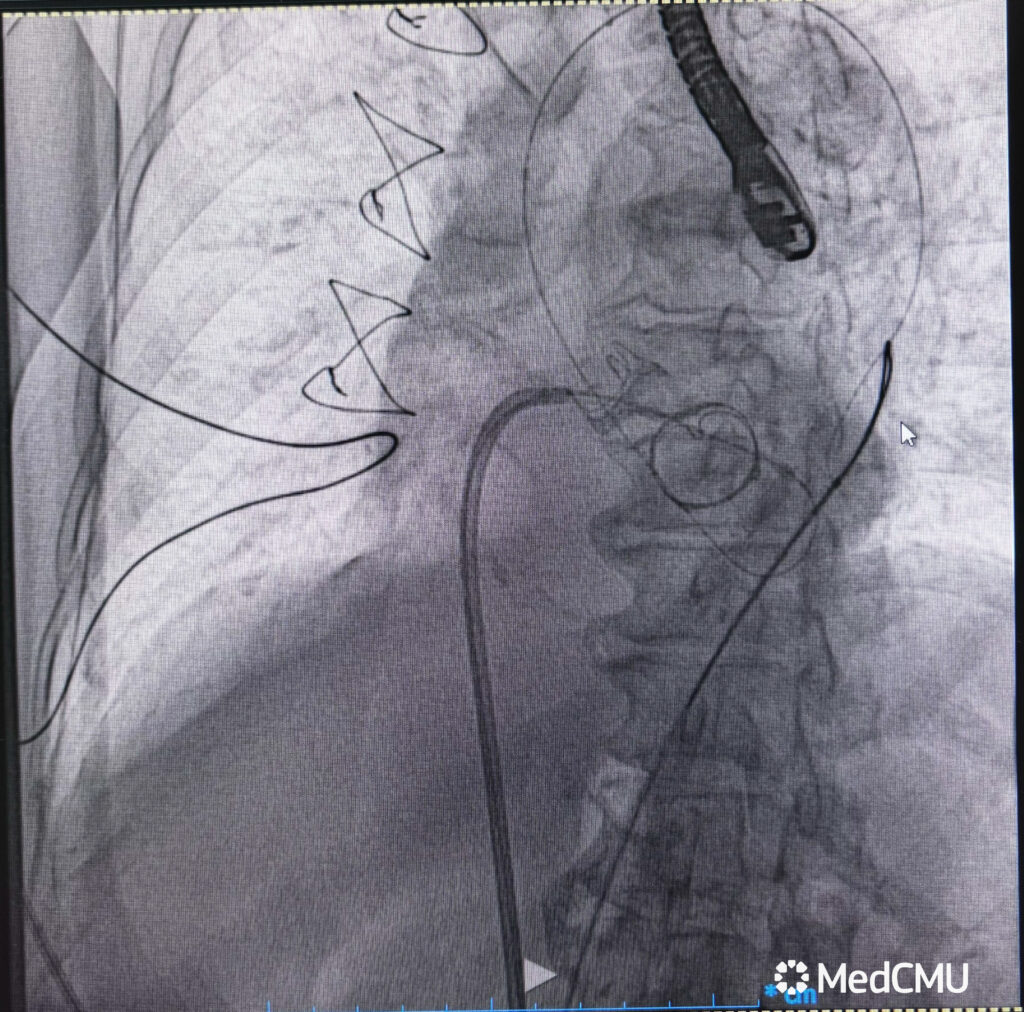

คณะแพทยศาสตร์ มหาวิทยาลัยเชียงใหม่ ประสบความสำเร็จในการรักษาผู้ป่วยหญิงไทย วัย 83 ปี ด้วยเทคนิคการเปลี่ยนลิ้นหัวใจไมตรัลเทียมตัวใหม่ แทนที่ตัวเก่าที่เสื่อมสภาพ ผ่านทางสายสวน โดยเทคนิคการตัดลิ้นหัวใจอันเดิม (LAMPOON – Laceration of the Anterior Mitral Leaflet to Prevent Outflow Obstruction) ถือเป็นรายแรกในระดับภูมิภาคของประเทศไทย ที่มีการทำหัตถการดังกล่าว และเป็นความก้าวหน้าสำคัญในการดูแลผู้ป่วยโรคหัวใจซับซ้อน

ผู้ป่วยรายนี้เคยเข้ารับการผ่าตัดเปลี่ยนลิ้นหัวใจไมตรัลชนิดเนื้อเยื่อมาแล้วเมื่อ 15 ปีก่อน แต่ภายหลังเกิดการตีบซ้ำ ส่งผลให้มีอาการหัวใจวายเฉียบพลันหลายครั้งในรอบสองเดือนที่ผ่านมา การรักษาด้วยวิธีมาตรฐานต้องอาศัยการผ่าตัดเปิดทรวงอกเพื่อเปลี่ยนลิ้นหัวใจเทียมชิ้นใหม่ ซึ่งมีความเสี่ยงสูงมากในผู้สูงอายุ คณะแพทยศาสตร์ มหาวิทยาลัยเชียงใหม่ จึงได้บูรณาการความเชี่ยวชาญของทีมแพทย์ด้านหัวใจ (Heart team) เพื่อใช้เทคนิคใหม่ที่ปลอดภัยกว่าและเลี่ยงการผ่าตัดใหญ่

อ.พญ.ทรรศลักษณ์ ทองหงษ์ เปิดเผยว่า “เทคนิค LAMPOON ถือเป็นก้าวใหม่ของหัตถการในการรักษาภาวะแทรกซ้อนของการใส่ลิ้นหัวใจเทียม เนื่องจากต้องอาศัยความแม่นยำสูงในการเลาะพังผืดและกรีดลิ้นหัวใจเดิม เพื่อป้องกันการอุดกั้นทางออกของหัวใจ การทำหัตถการนี้ต่างจากการเปลี่ยนลิ้นหัวใจด้วยสายสวนแบบทั่วไป เพราะผู้ป่วยมีลิ้นหัวใจเทียมชนิดเก่าอยู่แล้วซึ่งเสื่อมสภาพจนทำให้เกิดภาวะแทรกซ้อน ซึ่งหากเป็นวิธีการเดิม ผู้ป่วยจำเป็นต้องรับการผ่าตัดเปิดทรวงอกซ้ำซึ่งมีความเสี่ยงสูงมาก แต่ในครั้งนี้ ทีมแพทย์สามารถทำได้สำเร็จ และผู้ป่วยฟื้นตัวได้โดยไม่ต้องเปิดทรวงอก ถือเป็นก้าวสำคัญในการดูแลผู้ป่วยหัวใจที่ซับซ้อน”